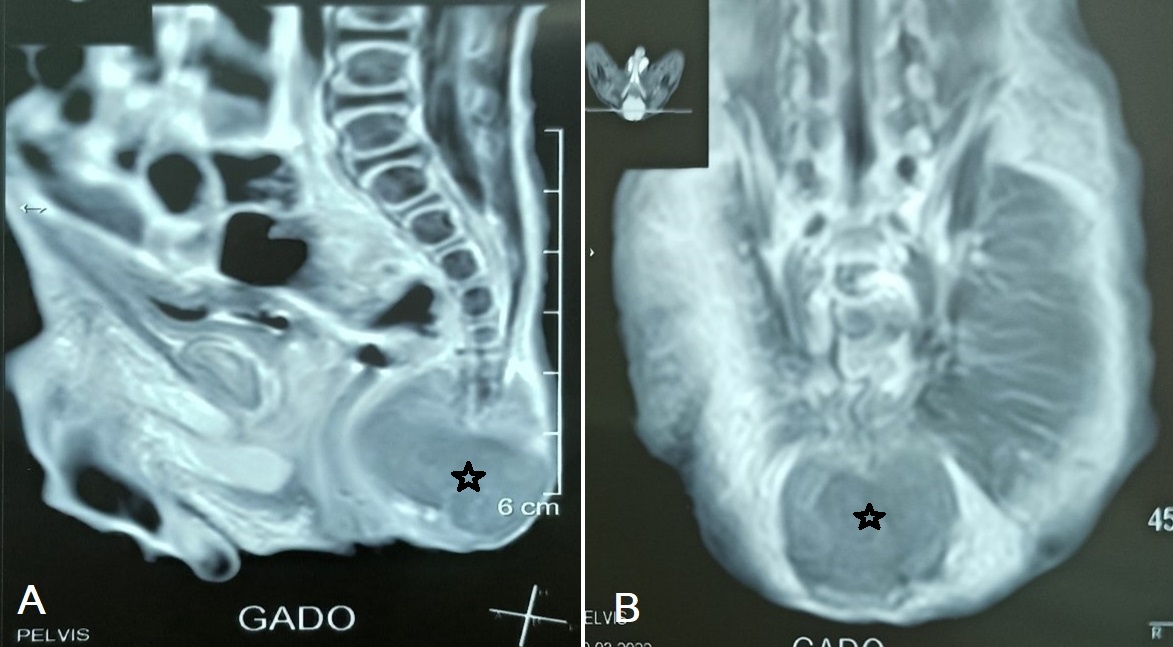

A full-term male baby was delivered by normal vaginal delivery. On routine neonatal examination, a swelling was noticed in the sacrococcygeal region. The swelling was firm and round, 5 x 7 cm in size, in the sacral region with normal overlying skin (Fig. 1). The abdomen was not distended, and no mass was palpable. This mass was not detected on antenatal ultrasonography. After clinical evaluation, Serum alpha-fetoprotein was 401ng/ml. Urinary vanillylmandelic acid and homovanillic acid were not performed preoperatively. Magnetic resonance imaging revealed a presacral mass extended downward and encasing the fifth sacral vertebra and the coccyx (Fig. 2A, 2B). Based on the clinical and radiological findings, the diagnosis of sacrococcygeal teratoma was made.

Figure 2

(A and B): MRI with GADO (in both sagittal and coronal section indicated by an asterisk) showing presacral mass extended downward and encasing the fifth sacral vertebra with the coccyx.